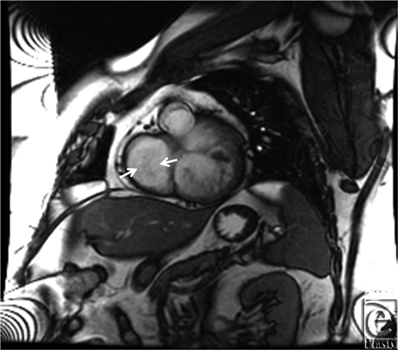

Initial 2D echocardiogram showed severe mitral valve regurgitation with a left ventricular ejection fraction of 35%. Furthermore, the valvular anatomy appeared peculiar; based on right ventricle (RV) and left ventricle morphology, CCTGA was suspected. A transesophageal echocardiography (TEE) was performed for further evaluation. It confirmed our diagnosis of CCTGA. Also, the (TEE) showed a hypertrophied RV and severe systemic AV (SAV) valve regurgitation (Figs 1 and 2). There was no evidence of an atrial septal defect, VSD, or patent ductus arteriosus. An MRI (magnetic resonance imaging) was performed to elucidate the anatomy. It affirmed the diagnosis of CCTGA with a trileaflet SAV that demonstrated severe regurgitation from the systemic ventricle (SV) to left atrium (Figs 3-6). Because of the patient's symptoms and severity of the regurgitation of the SAV, we decided to perform SAV replacement. Preoperative cardiac catheterization showed left dominant coronary circulation with left circumflex and a ramus intermedius originating from left cusp through separate ostia (Figs 7 and 8). Left anterior descending artery originated from proximal right coronary artery through a single ostium from right coronary cusp (Figs 8 and 9). No obstructive coronary heart disease was found and the patient proceeded to surgery.

![]() |